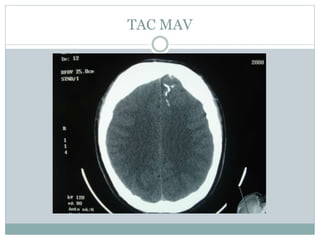

TAC MAV

Epilepsia-Malformacion AV